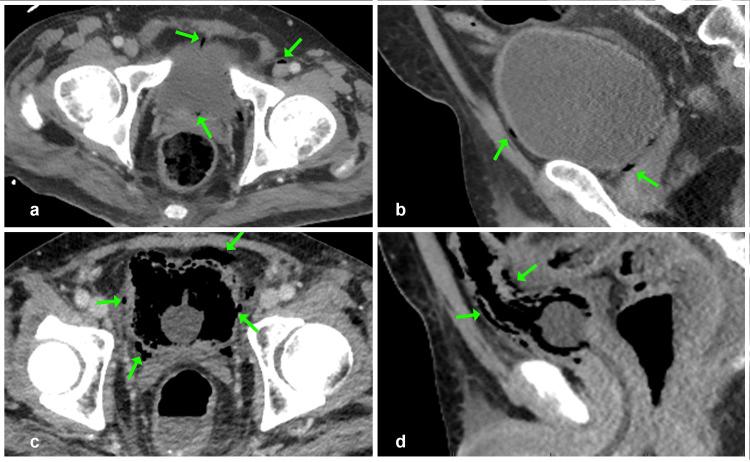

We describe the first documented case of ventriculitis complicating (SS) hyperinfection syndrome (SHS). A 40-year-old immunosuppressed Indigenous man from a hyperendemic region presented with septic shock from a resistant () emphysematous cystitis (EC). Diagnostic challenges related to cirrhosis and atypical SS presentation delayed recognition, culminating in ventriculitis confirmed on magnetic resonance imaging (MRI) and cerebrospinal fluid (CSF) culture. Targeted parenteral antibiotics and ivermectin led to full recovery after a prolonged admission and rehabilitation process. This case underscores several critical clinical lessons: empirical daily ivermectin should be strongly considered for patients with sepsis from hyperendemic regions, as it may be lifesaving. Awareness of the hyperendemicity of SS in certain regions of Australia is crucial, as it can precipitate life-threatening septicaemia and central nervous system infections. The cumulative impact of immunosuppressive factors such as diabetes, alcohol dependence, and malnutrition warrants careful evaluation in such patients, as they are easy to overlook. Finally, this case expands our understanding of the pathogenic potential of , a bacterium rarely represented in the current literature.